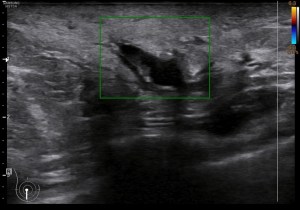

El caso que os traigo hoy es muy sencillo, es una mastitis. Vemos muchas en la sección de mama, pueden cursar con calor local, dolor, piel de naranja y fiebre. Las mastitis habitualmente son valoradas clínicamente y diagnosticadas sin necesidad de realizar ecografía de mama, pero en ocasiones, si el tratamiento farmacológico no funciona, hay que realizar ecografía para valorar posibles complicaciones como abcesos o lesiones tumorales subyacentes.

La clínica ya la conocemos, la semiología os la presento aquí. Ecográficamente la mastitis se ve como una zona donde el tejido varía la ecogenicidad, se vuelve más hiperecogénico, aumena su tamaño, incluso su vascularización. La piel se puede ver engrosada. El tejido mamario puede verse heterogéneo, simulando lesiones de otra índole, es decir, su aspecto puede ser variado.

Ecográficamente, encontraremos una zona afectada, de la manera descrita en el párrafo superior, y junto a ella, en una zona normal, sin afectación la semiología normal de la mama.

Te presento una mastitis tipo, con un componente de resistencia al antibiótico, con lo que la paciente no mejoraba pese al tratamiento, además presentaba una colección con un tracto que abocaba en la superficie y drenaba líquido purulento a la superficie.

La imagen 1 y la imagen 2 son normalidad con anatomía básica y semilogía patológica respectivamente. Compara amabas imágenes para darte cuenta de como cambia el tejido afecto por la mastitis en este caso. No olvides que hay otras patología que pueden afectar el tejido modificando su ecoestructura normal de forma similar.

En la imagen 3 puedes ver un absceso, complicación de una mastitis, cuyo aspecto es el de una colección anecoica, que si observas, quieres buscar la superficie de la piel. La imagen 4 y 5 es el estudio de la lesión en trasnverso u otro plano y el estudio doppler buscando posible vascularización a ese nivel.

En las mastitis, al ser procesos infecciosos, no es raro ver gánglios intramamarios aumentados de tamaño o reactivos que hayan perdido su centro graso. En este caso, en localización muy próxima. Observa el aspecto habitual en forma de judia con centro hiperecogénico graso y corteza hipoecogénica, imagen 4.